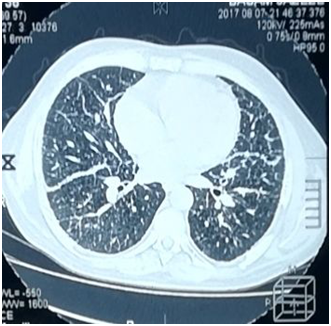

Chest Multi-Slice CTscan revealed several diffused interstitial reticular densities in both pulmonary fields with small nodular densities without enlargement of lymphatic nodes (Figure 3). Pelvis Multi-Slice CT scan revealed lytic lesions in hip and legs without invasion of adjacent tissues (Figure 4). We sent the Bronchial incisional biopsy taken by bronchoscopy and surgical incisional biopsy taken from left tibia to pathology department.

Figure 3 Chest MSCT showing several diffused interstitial reticular densities in both pulmonary fields with small nodular densities.

Pulmonary involvement is observed in 20-40% of LCH patients and can give symptoms, such as pneumothorax, dyspnea, tachypnea, and cough. Imaging studies of the lungs may reveal cysts and micronodular infiltrates.7 The patient had grade II dyspnea. CXR and MS- CT imaging of the lungs showed diffused interstitial reticular density. We performed Bronchoscopy and biopsy that showed histological features consistent with LCH.